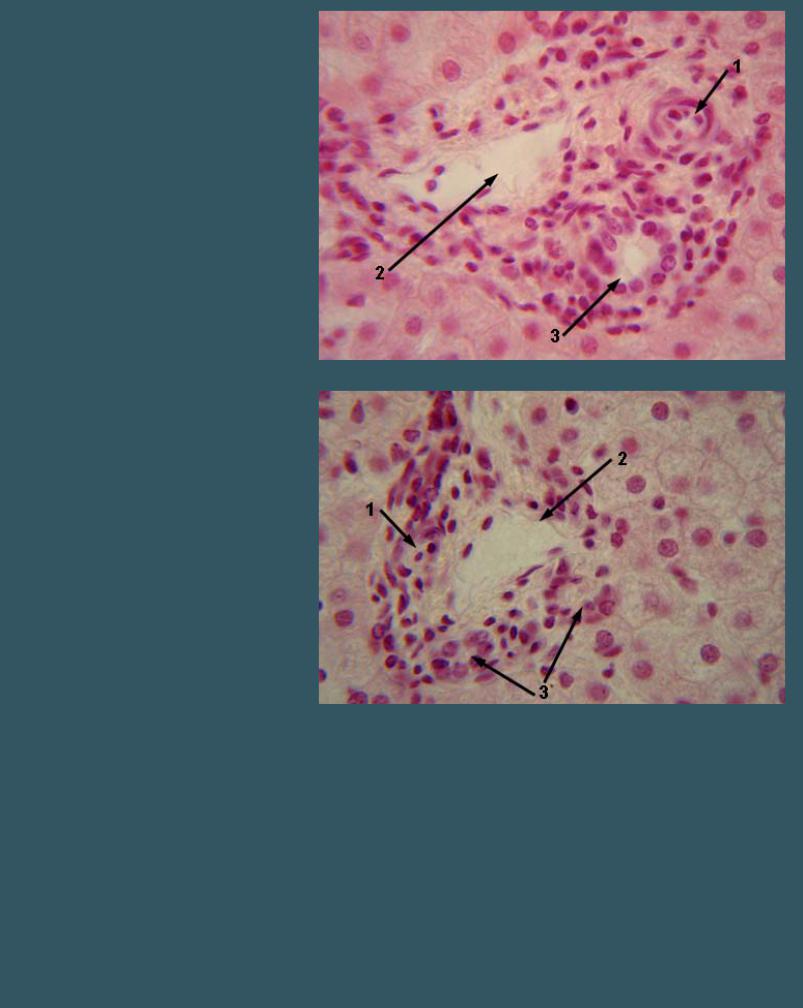

Окраска гематоксилин-эозином

1 - артерия

2 - вена

3 - желчный проток

4 - гепатоциты 1, 2, 3 - триада печени

ПЕЧЕНЬ

Окраска гематоксилин-эозином

1 - артерия

2 - вена

3 - желчный проток

4 - гепатоциты 1, 2, 3 - триада печени

ПЕЧЕНЬ

Окраска гематоксилин-эозином

1 - артерия

2 - вена

3 - желчный проток 1, 2, 3 - триада печени

ПЕЧЕНЬ

Окраска гематоксилин-эозином

1 - артерия

2 - вена

3 - желчный проток 1, 2, 3 - триада печени